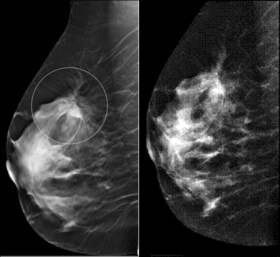

Le centre d’imagerie médicale est très impliqué dans le dépistage du cancer du sein (ADECA 75).

Toute anomalie décelée n'est pas forcément un cancer.

Tous les cancers du sein ne sont malheureusement pas détectables par la mammographie.